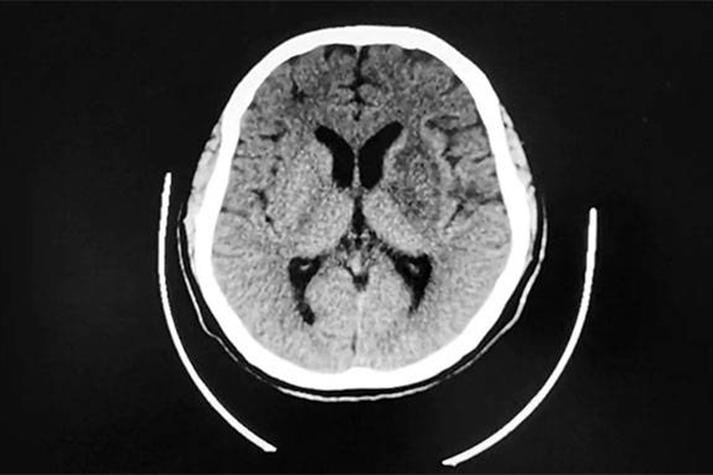

- 慢性期(>1-2周):坏死的细胞被清除,形成囊腔,水分子又可以自由活动了,病灶在DWI上的高信号会消失,变为等信号或低信号,在ADC图上信号恢复正常。